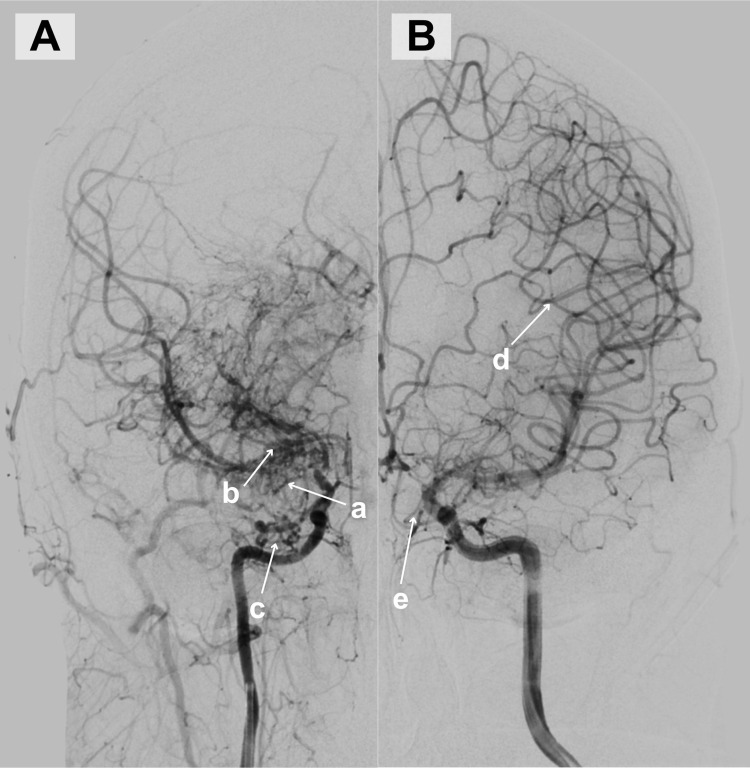

Case report: In this article, we describe the clinical case of a 48-year-old woman who presented with sudden-onset weakness in her left arm. Imaging studies demonstrated acute ischemia in the territory supplied by the right middle cerebral artery. Further evaluation with computed tomography angiography revealed compression of the right internal carotid artery by the hyoid bone. However, additional imaging studies, including digital subtraction angiography and carotid Doppler ultrasound, did not reveal any signs of internal carotid artery stenosis. This suggested that the compression was functional, occurring only in specific positions of the head or arms. The patient was also newly diagnosed with Moyamoya syndrome, characterized by progressive stenosis of the intracranial vessels. Prompt recognition of these findings enabled timely management, including the initiation of antiplatelet therapy.